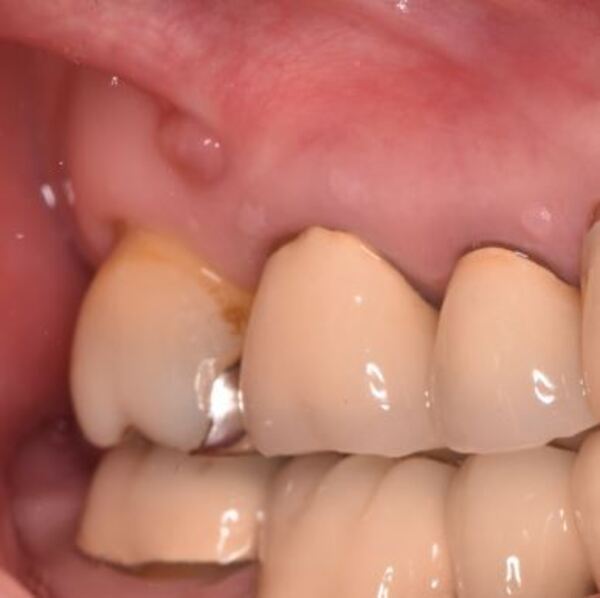

術前のデンタルX線写真と口腔内写真です。左下の一番奥の歯(#37)です。

左下の親知らずは1ヵ月ほど前に抜いたそうです。

親知らずと隣り合っていた歯の後ろ側(遠心)から虫歯が進行しています。

診査の結果、神経は正常に生きていることが分かりました。その為、いきなり神経は取らずに虫歯を取り切った上で神経を温存する治療を進めていくこととなりました。